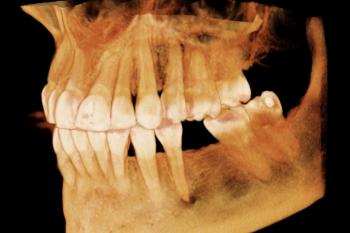

Gendex Digital Imaging (GS-700)

Utilizing the latest sensor technology, the GXS-700 system delivers real-time images of truly amazing clarity and detail — greatly supporting diagnosis and treatment. When compared to traditional film radiographs, the digital system can significantly reduce patient exposure to radiation and eliminates the need for working with film processing chemicals.